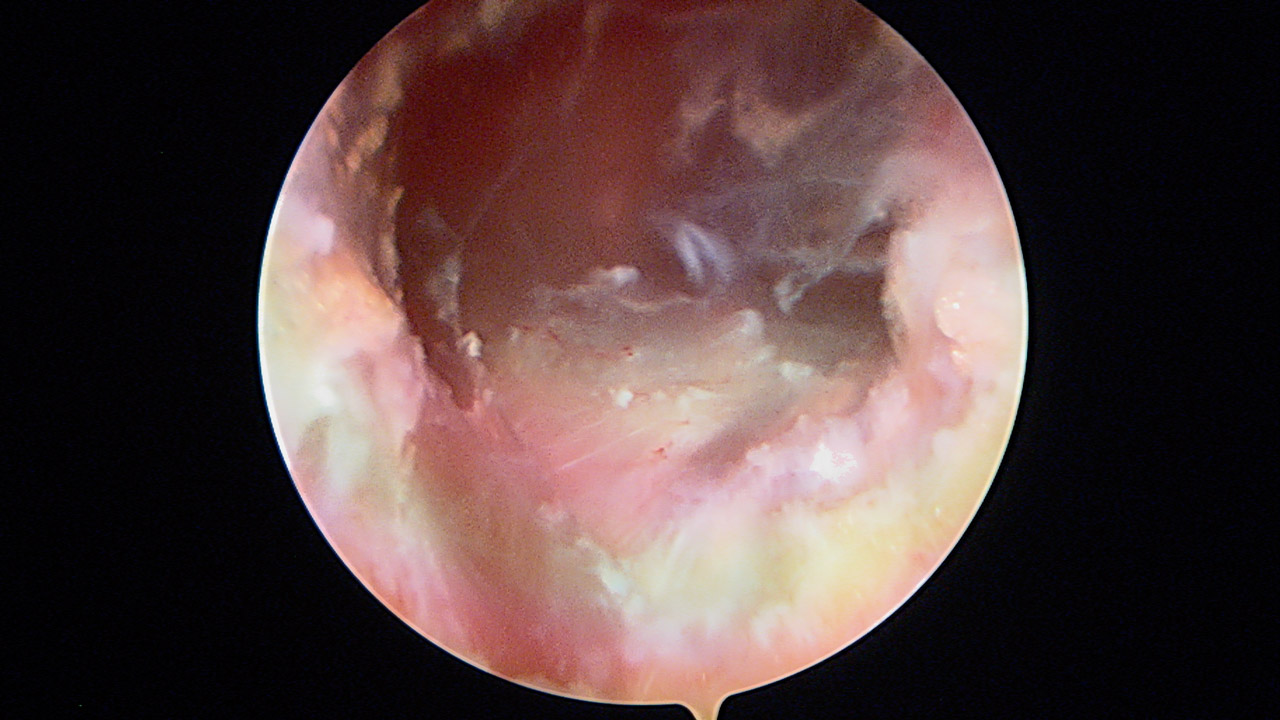

Paso 1: plicatura inferior

Una vez intraarticular, se explora el labrum y los ligamentos, con un gran receso inferior. Realizamos una plicatura con un anclaje Iconix® 1,4 (Stryker, Kalamazoo, Mi) posteroinferior que se deja sin anudar y otro anclaje Iconix® 1,4 anteroinferior exactamente igual y simétrico. Con este gesto, se pretende retensar el LGHI, tanto anterior como posteriormente, los cuales se anudarán al terminar la ligamentoplastia (Figura 4).